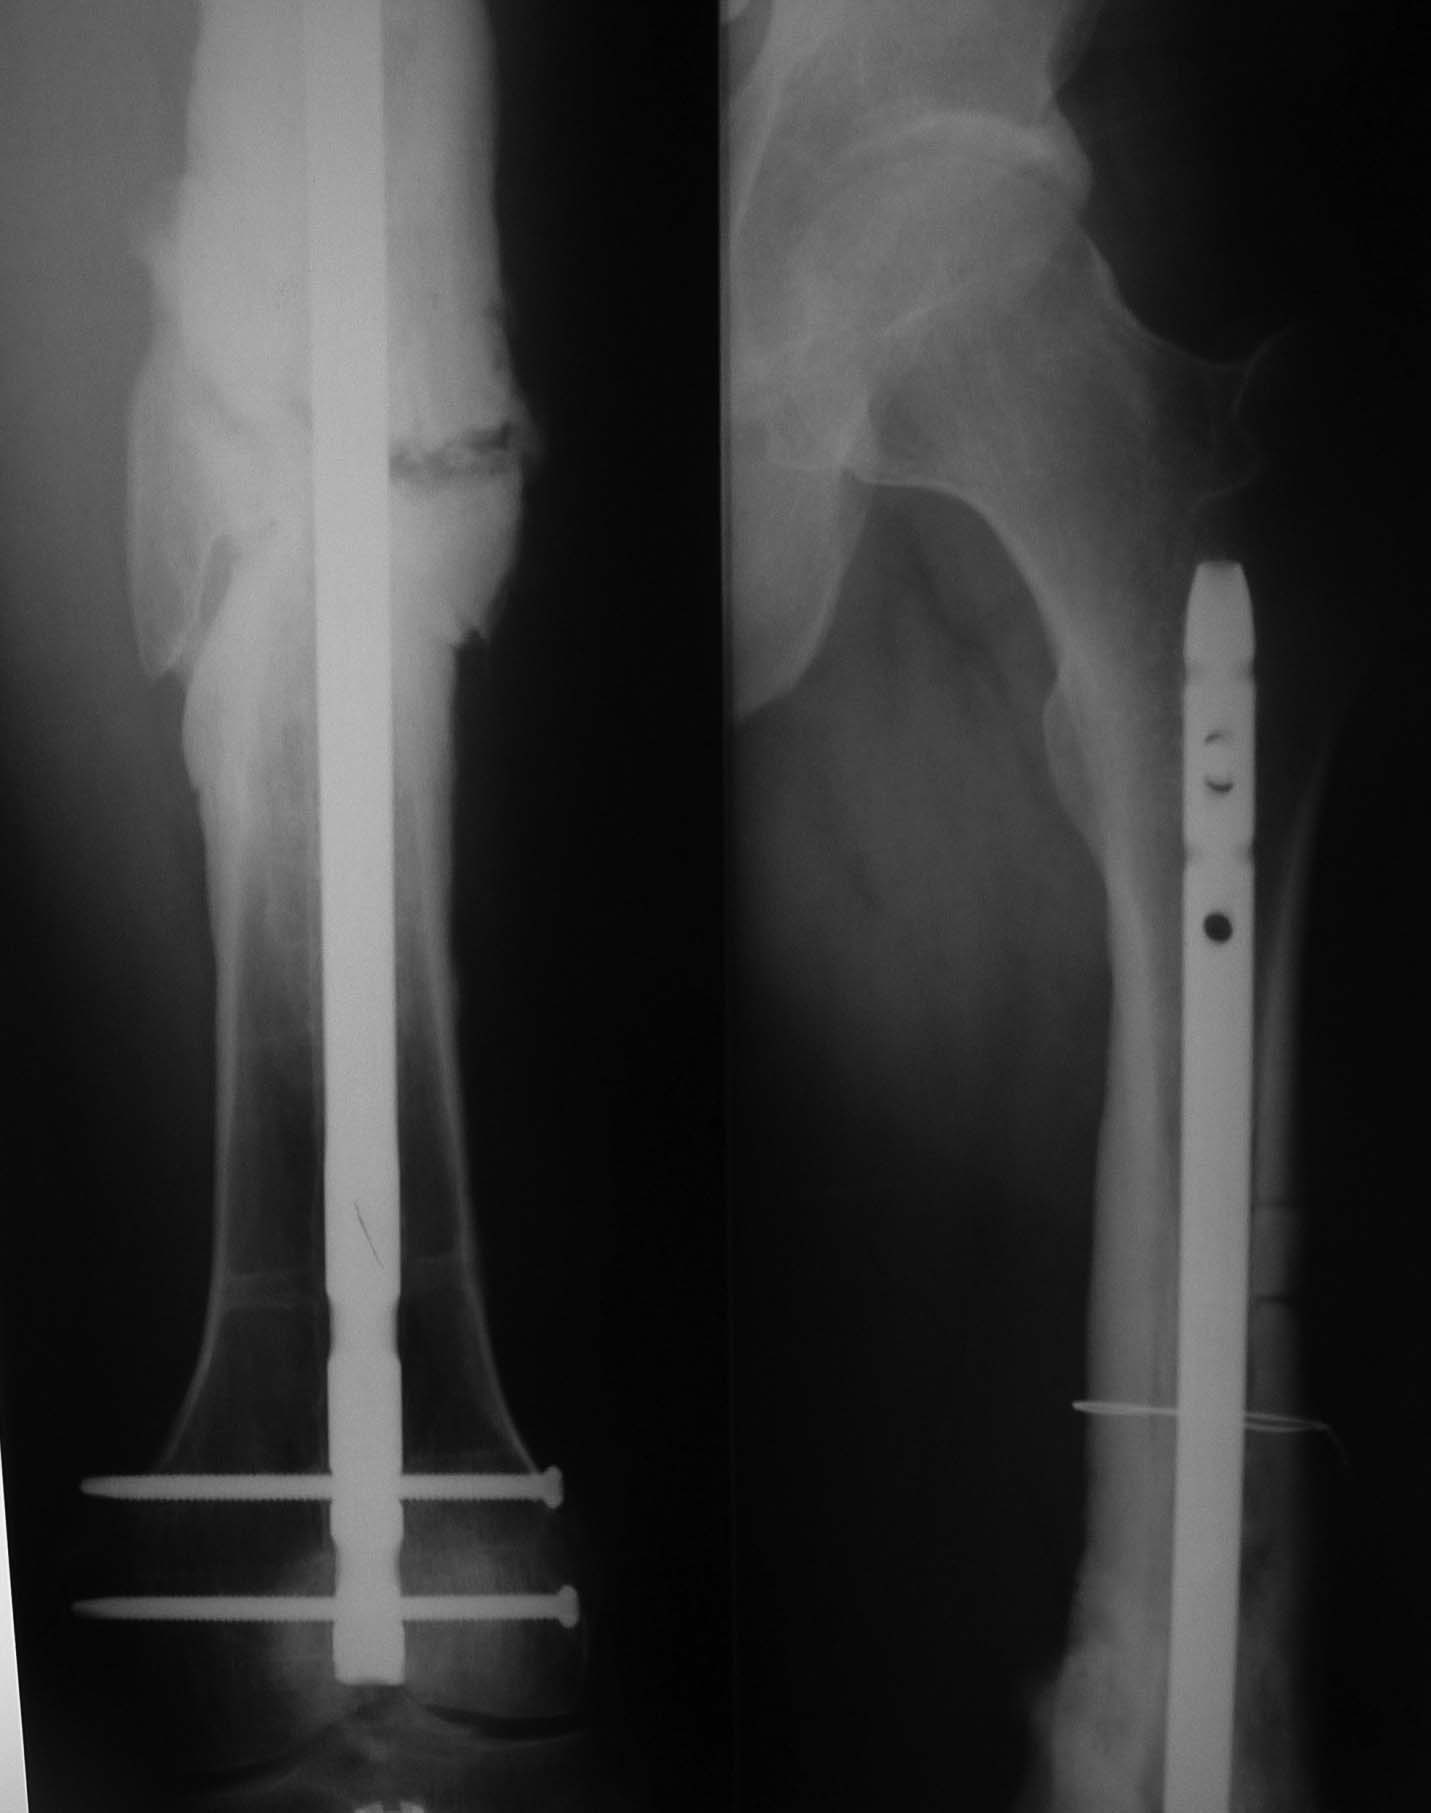

У Синтеза есть хороший набор для этих целей. С возможностью охлаждения формируемого канала и забора аутостружки. Вариант не очень бюджетный и развертки достаточно агрессивные. Нужен постоянный контроль, чтобы не пенетрировать кортикальный слой. Во вложении пример. Правда тоже не голени, а верхней 1\2 бедра (снимки до и через 3 мес после операции).